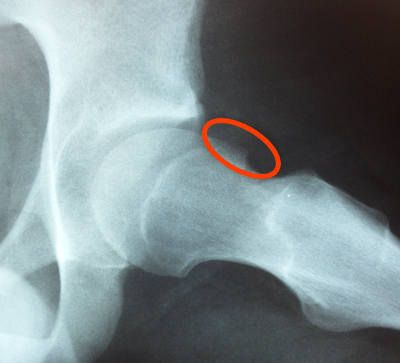

Sometimes loose bodies – typically from cartilage or bone – can cause instability of the hip joint. This can lead to a sudden, sharp pain in the hip, sometimes causing a fall.

Synovitis is an irritation or inflammation of the lining inside the hip joint, commonly seen with other problems inside the joint. Synovitis is treated with debridement using specialized shavers. Hip arthroscopy can trim out the unstable cartilage, or in some cases perform a microfracture of the bone to stimulate the growth of new cartilage.

Hip arthroscopy can trim out the unstable cartilage, or in some cases perform a microfracture of the bone to stimulate the growth of new cartilage.